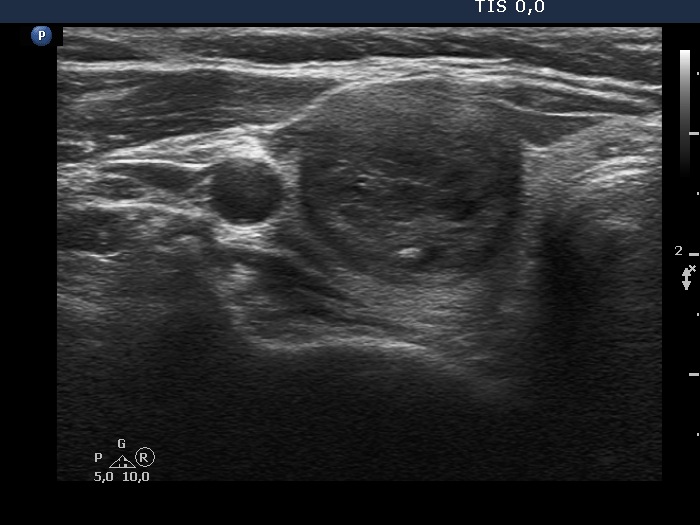

Extrathyroidal spread - case 2128 (ultrasonographic picture 2)

Right lobe, longitudinal scan

Right lobe, another transverse scan. The capsule is discontinuous at the medial part of the lobe.